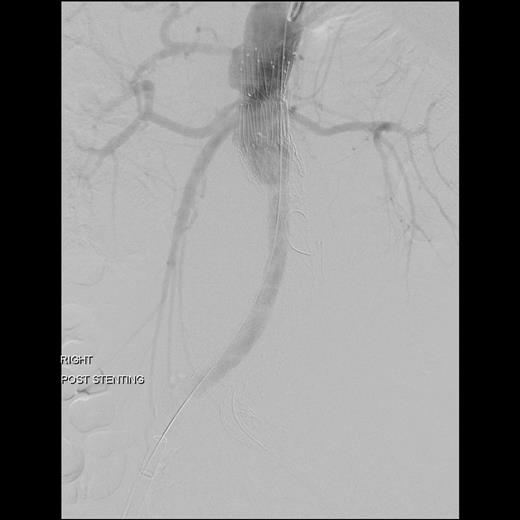

Surgery was performed in hybrid operating theatre. The aorta was accessed via bilateral groin cut-downs to expose both common femoral arteries. Intra-operatively, the type IIIa endoleak was excluded using a right-sided Cook aortouniiliac stent graft (AX1-1-36-116). The left renal arteries were cannulated from the left brachial artery. A PTFE-covered nitinol stent (Atrium V12) was advanced into the left renal artery and deployed in a chimney fashion. The left iliac limb of the stent was occluded using a 20 mm Amplatzer plug proximally and distally with Iliac Plug Zip 24 and 30 mm. Femorofemoral crossover bypass was then performed to complete the surgery. The completion angiography showed adequate sealing with no endoleak (Figs 2 and 3).

The completion angiography showed adequate sealing with no endoleak.